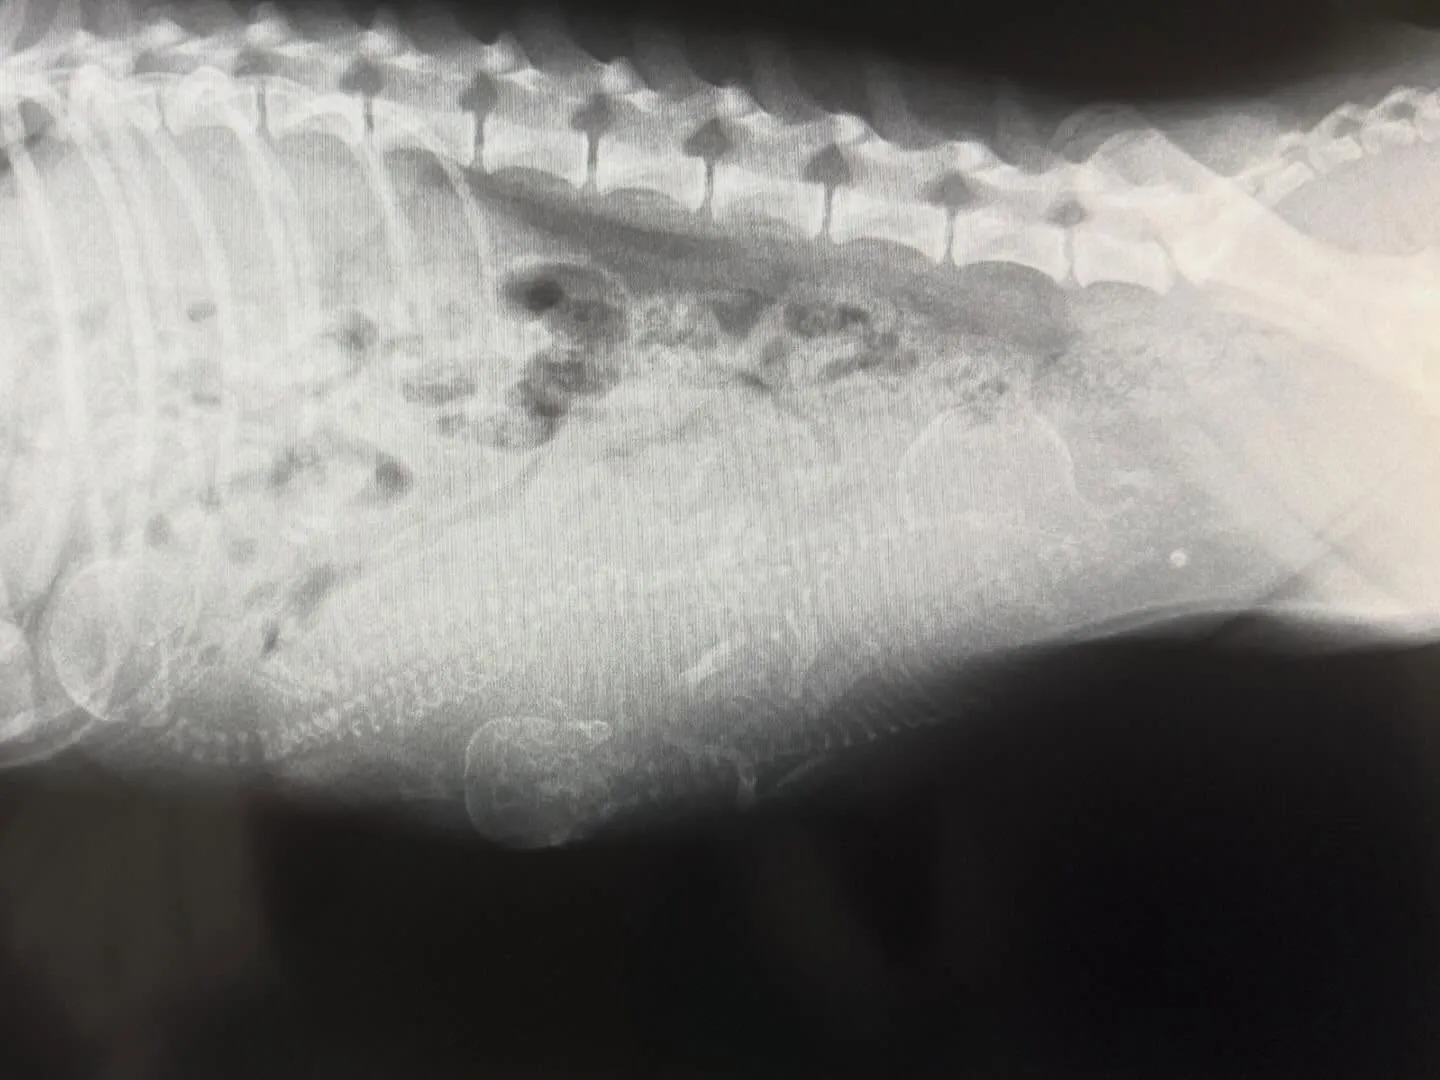

予定日より少し早く産まれましたが、3ワンともしっかり育っていて元気です♡

14時00分 長男

15時26分 長女

16時10分 次女